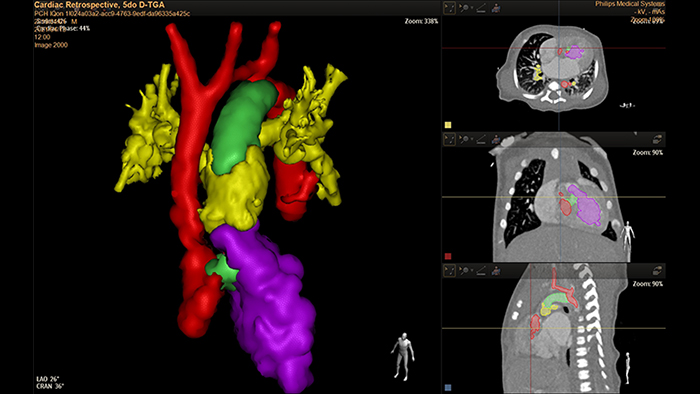

Analiza D-TGA z użyciem systemu HeartNavigator u 5-dniowego noworodka

Modelowanie 3D z użyciem systemu IntelliSpace Portal